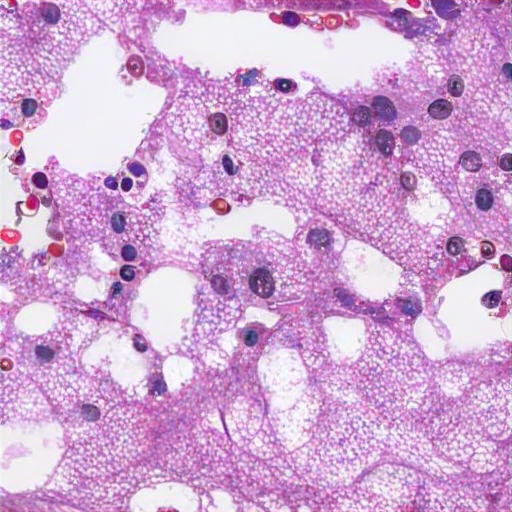

The renal tissue image displays clear cell renal cell carcinoma (RCC) characterized by cells with clear cytoplasm, round to oval nuclei, prominent nucleoli, and a rich vascular network. The clear cell cytoplasm dissolved in the cytoplasm due to dissolved and eosinophilic and pleomorphism. The tissue architecture is distorted, lacking normal renal structures, suggesting the malignancy, the most common subtype of renal carcinoma. L regions show clear cytoplasm, dissolved due to lipids/carbohydrate accumulation or carbohydrates, and stromal necrosis, significant vascular invasion. These features indicate a renal neuroendocrine subtype of lateral carcinoma, specifically clear cell RCC. Nuclei are visible post-staining, with abundant cytoplasm due to dissolved lipids and unremarkable nuclei. No organized glomeruli or tubules is visible, further support the diagnosis, characterized as renal cell carcinoma or a tubular-inian neoplasm.